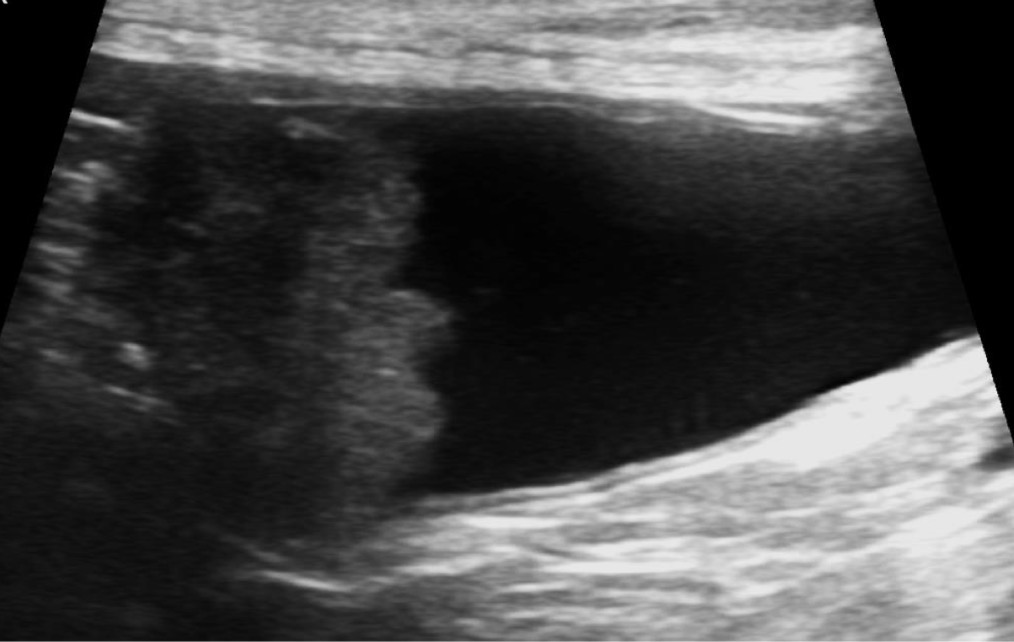

Polycystic kidney disease

What is occurring in this patient?